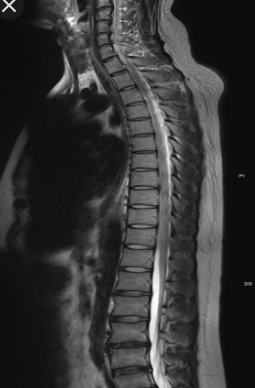

MRI 건강보험 적용